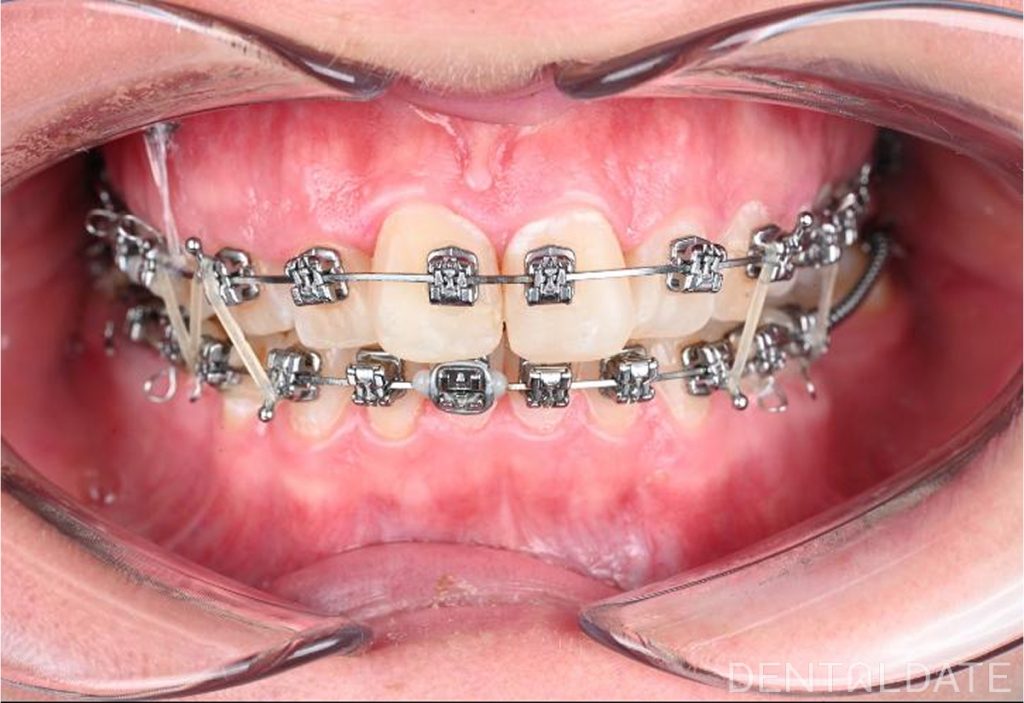

This case demonstrates the placement of an interradicular miniscrew. The procedure is performed under local anesthesia and is completely painless. The procedure, from the administration of anesthesia to the control radiograph, takes approximately 10 minutes. Screw position is verified using cone-beam computed tomography (CBCT), currently considered the gold standard in dentistry.